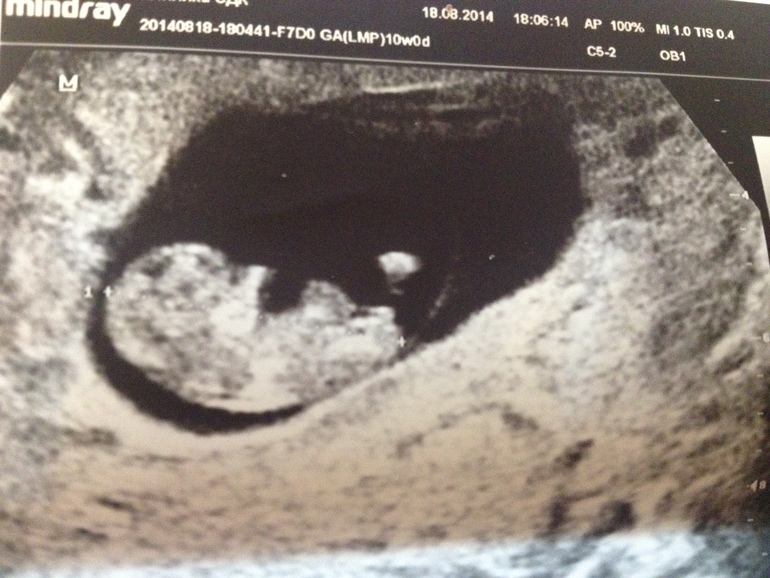

Вообще это УЗИ для нас уже седьмое, кажется. В начале беременности из-за осложненного анамнеза ходила на исследование раз в неделю - смотрели, есть ли сердцебиение, потом как прогрессирует беременность.

Это исследование на сроке 10/11 недель - 18.08.2014 г.